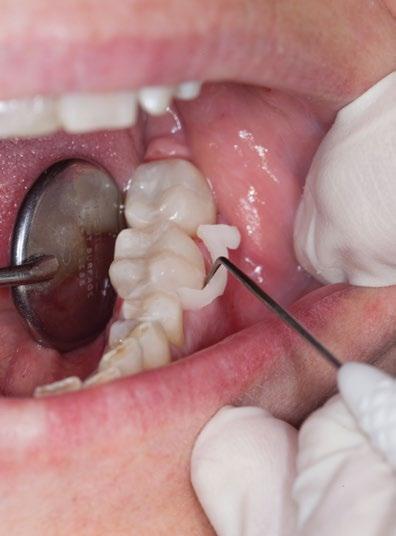

"Unabhängig vom Feilensystem werden bis zu 35% der Kanalwände nicht durch die Instrumente berührt."

Peters O.A. et al. Effects of Four Ni-Ti Preparation Techniques on Root Canal Geometry Assessed by Micro Computed Tomography. Int Endod J 2001. 34(3):221-30